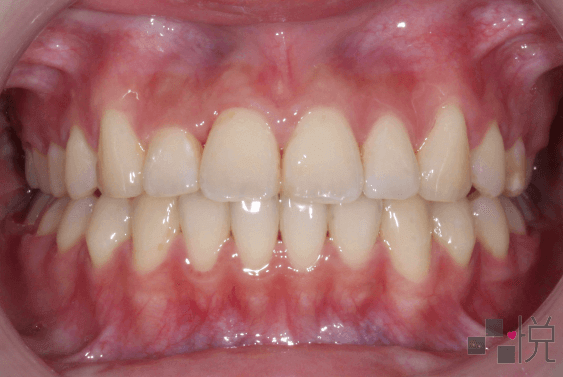

本案例矯正前是「假性戽斗」,齒列擁擠、深咬,還合併有前牙及後牙錯咬。

選擇不開刀(正顎手術)只做牙齒矯正,拔除狀況不好的上顎右側犬齒,以上顎第一小臼齒取代上顎犬齒。

矯正治療後齒列整齊,恢復正常咬合(上排牙齒蓋在下排外側),明顯改善深咬的情形,同時也改善戽斗的臉部外觀。